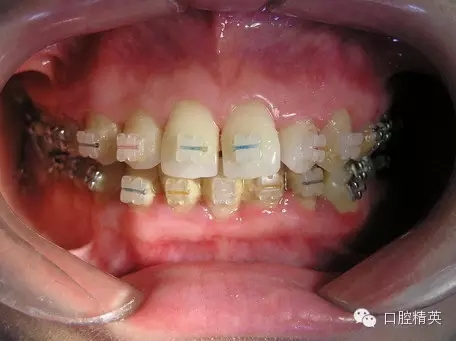

鄰面去釉臨床操作步驟組圖

圖2

3、在鄰面去釉、恢復牙冠外形后,應使用金剛砂條給鄰牙切割面進行精細打磨拋光;使之鄰面光滑,避免食物殘渣及菌斑的附著,減少齲病的發(fā)生(圖6~圖8)。

3、金剛砂條給鄰牙切割面進行精細打磨后,應常規(guī)給去釉牙面涂擦氟化鈉甘油糊劑;采用棉片或紗布粘氟化鈉甘油糊劑,拉鋸式涂擦方式效果較好(圖9~圖11)。圖12、圖13顯示去釉后的牙列狀況。

提示:這里博客文章列舉的鄰面去釉步驟不是一個病例的照片,是選用幾個病例不同去釉階段的照片組合而成。其中有裝配金屬托槽矯治器的,也有陶瓷托槽的,主要是給正畸專業(yè)網(wǎng)友朋友們介紹其臨床操作步驟要點。是一個階段性治療狀況,不是一個最終治療結(jié)果。好的經(jīng)驗給大家展示,需要注意之處也暴露給大家,以便引起大家關(guān)注。圖12、圖13病例是5年前我們最初去釉治療的狀況,牙冠外形和鄰接點的問題,當時我們是關(guān)閉間隙后采取二期修形處理的。